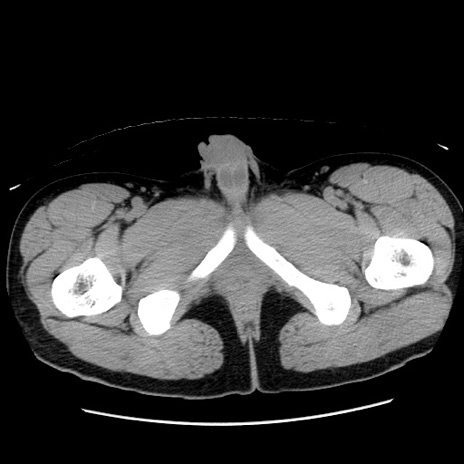

症例36(横断像)

【症例】20歳代 男性

【主訴】心窩部痛

【現病歴】今朝より上腹部痛あり。一旦軽快していたが再度出現したため救急要請。昨日夕に白身の魚を含む刺身を食べた。

【身体所見】BP 136/89mmHg、HR 74/min、BT 37.0℃、腹部:膨満、軟、心窩部に圧痛あり。反跳痛なし、筋性防御なし、腸雑音やや亢進あり。

【データ】WBC 17700、CRP 0.48